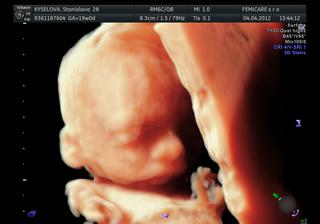

@michaelaamartin Ahoj, vsetky merania a morfologia sa robi na 2D, 3D je len komercna zalezitost pre mamicky. On ma uplne speci pristroj, robi normalne taky rez cez babatko, pozeral vsetky organy, srdiecko, tok krvi do srdca, mozog, meral koncatiny, pocital stavce.... trvalo to asi 35 minut, vsetko nam vysvetlil a sem tam prepol na 3D a z toho nam potom urobil super fotky🙂

@jeny Platila som 50 € a 10 € za fotku (vo velmi vysokej kvalite). Nie je to moj gynekológ, ja som isla k nemu len na toto vysetrenie. ked som mu volala, povedala som, ze chcem ist na morfologicky ultrazvuk. Bola som tam 19+0 podla MS, ale podla babatka som vraj o 4 dni menej.... Pohlavie nam povedal asi sekendu potom , co mi prilozil sono na brucho, vraj 100% chalan🙂

@nastasyk Ďakujem krásne za info. Tie 3D a 4D ultrazvuky sú síce drahšie ako inde, ale počula som o ňom, že je fakt profík vo svojej oblasti, že chodil aj na stáže niekde do zahraničia. A čo človek nespraví pre svoje bábatko? No a keď mi na 100% povie pohlavie, ktoré ešte stále neviem :D .....

@michaelaamartin jasne, myslim, ze len dvaja alebo traja lekari na Slovensku maju takuto specializaciu na geneticky ultrazvuk, takže urcite sa oplati priplatit si. Okrem toho, ja aj manzel sme mali z toho fantasticky zazitok🙂